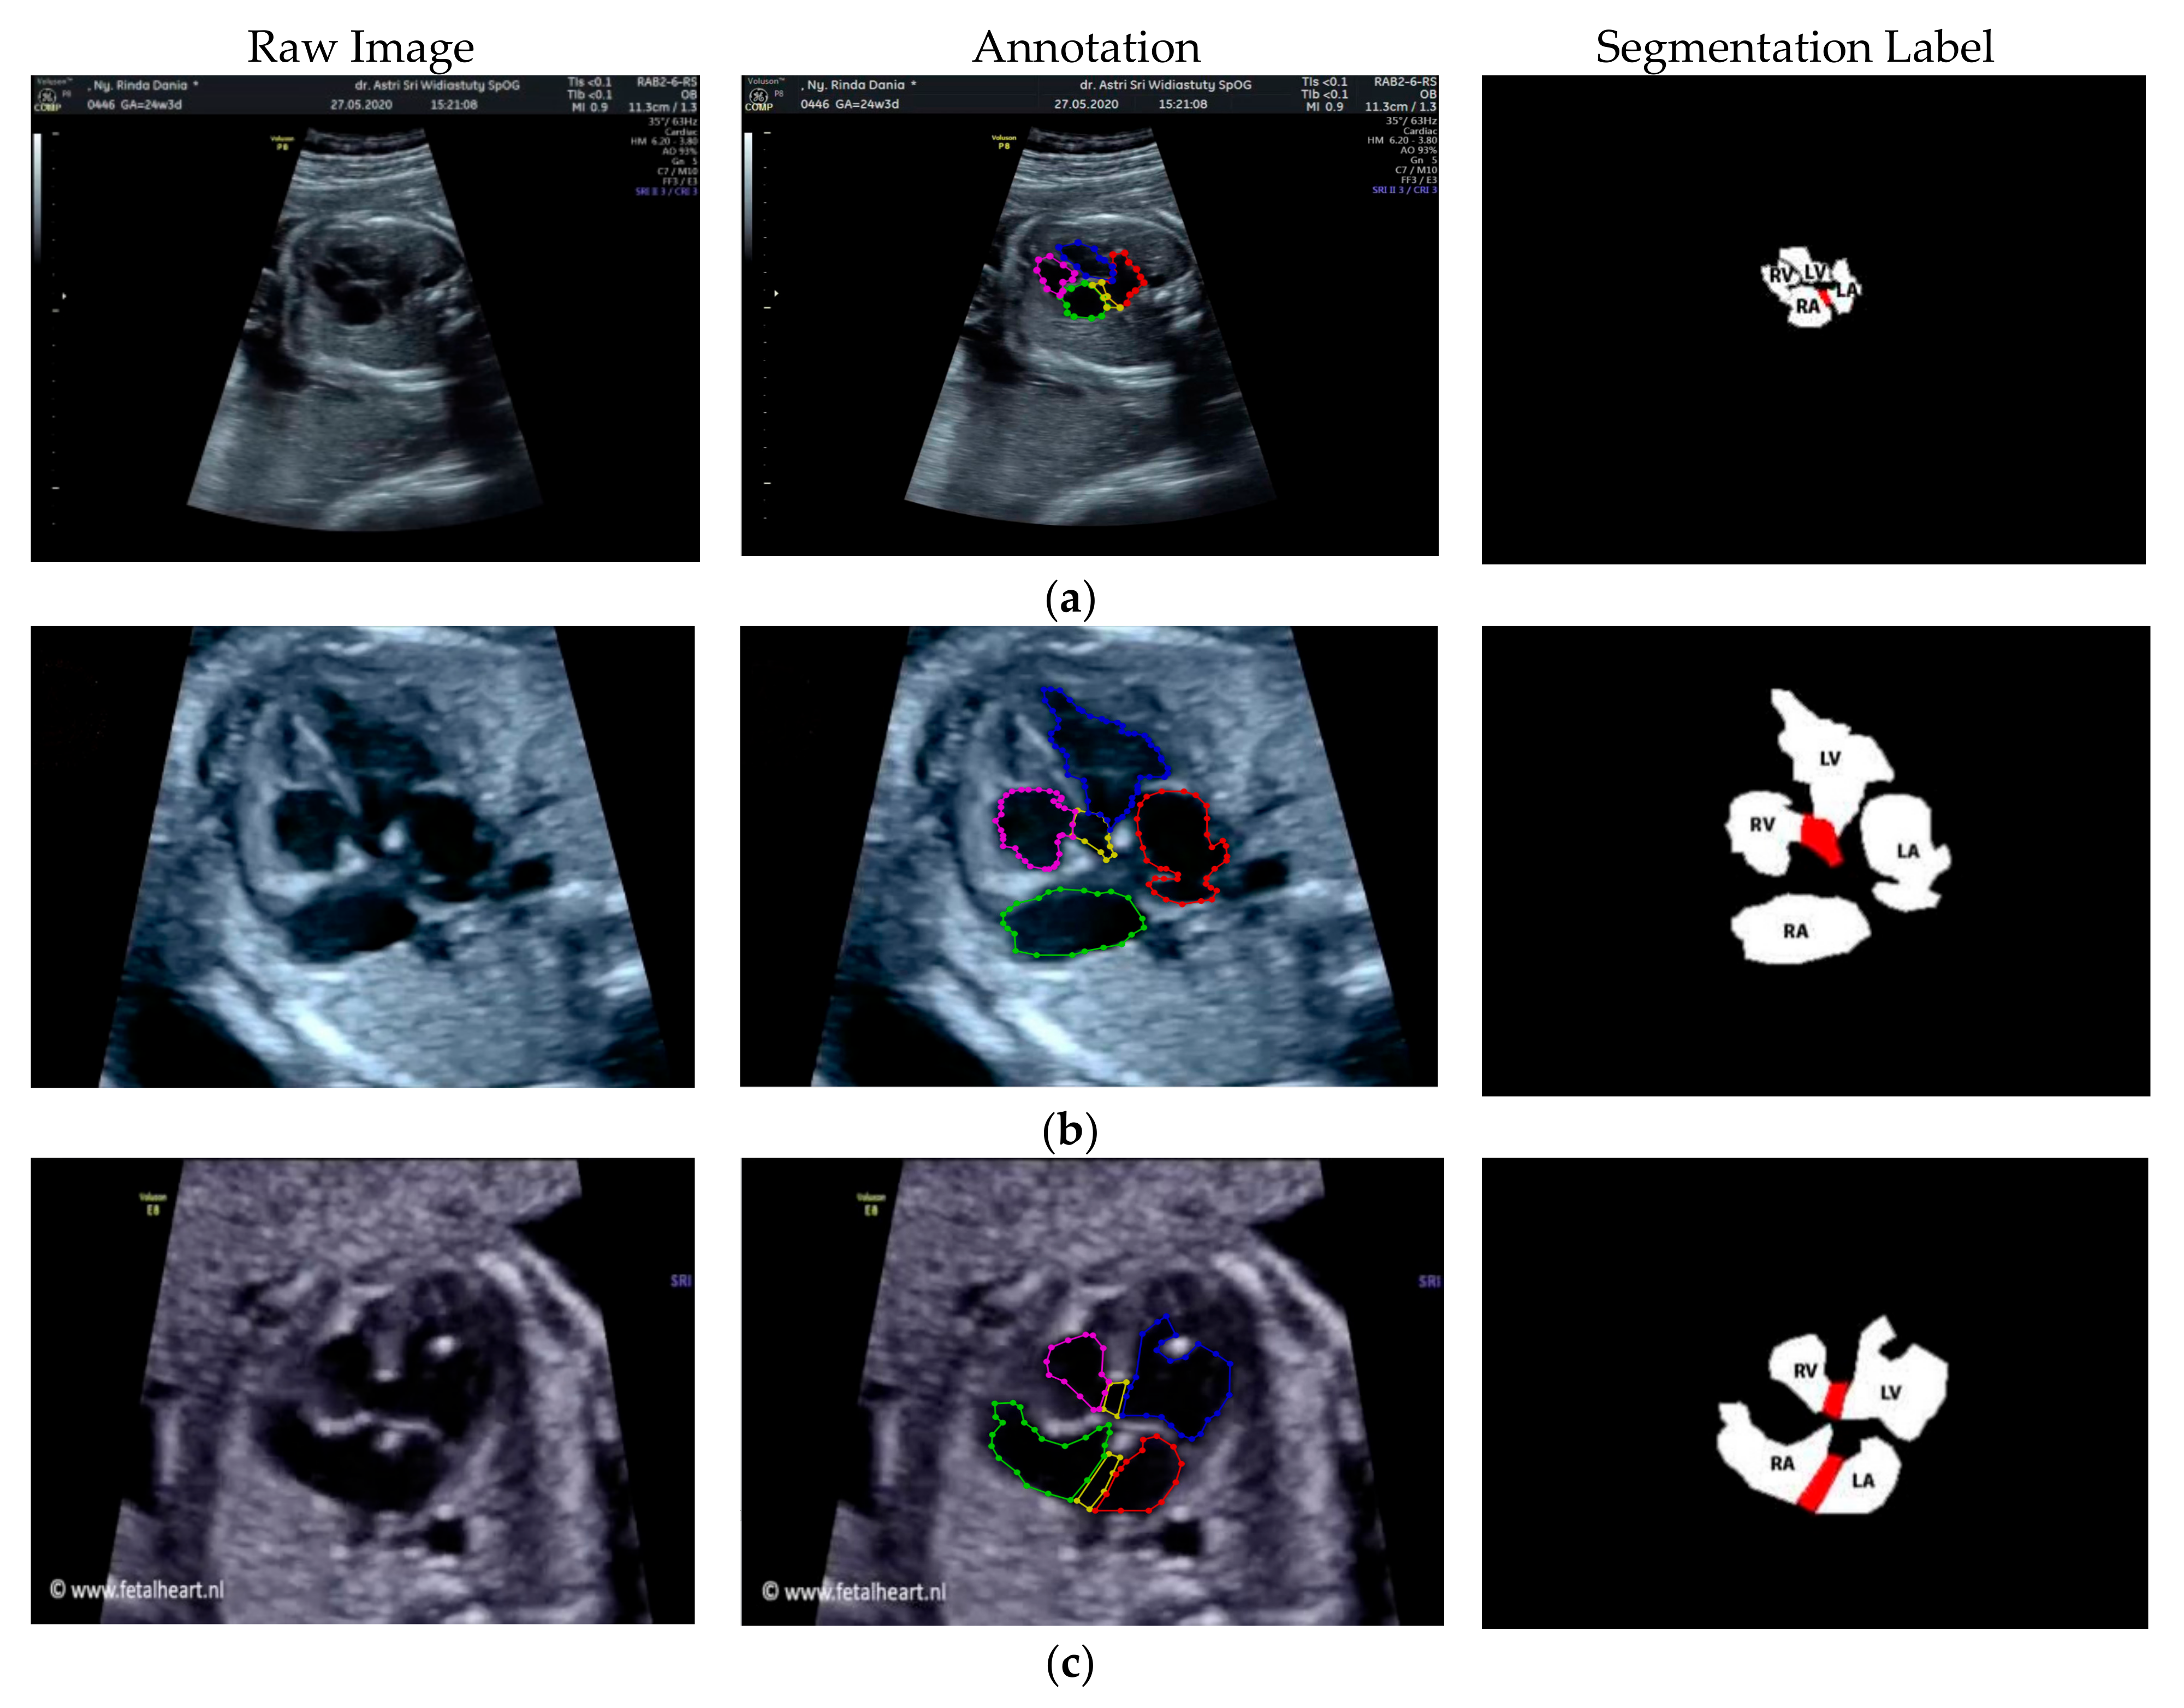

2.3. Image Annotation

The anatomical heart structures are critical for the segmentation process. The maternal–fetal clinician as the image annotator should drew precise boundaries around the heart images manually with data annotation tool (LabelMe) [7]. LabelMe to provide an online annotation tool to build image databases for computer vision research. The significant variations in image quality, shapes, sizes, and orientations between the pregnant women were used to create a database of ground truths. In the fetal echocardiography with normal anatomy, each standard view has a different structure of heart chamber; therefore, the annotation should be conduct for all standard views with their respective chamber such as, 4CH standard view consists of five heart chambers, i.e., Ao, LA, LV, RA, and RV; 3VT standard view consists of three heart chambers, i.e., DUCT, SVC, and AoA; LVOT standard view consists of five heart chambers, i.e., AoA, LA, LV, RA, and RV; and RVOT standard view consists of four heart chambers, i.e., DUCT, SVC, AoA, and MPA.

Especially for heart defect detection, only 4CH view was used to analyze ASD, VSD, and AVSD images. Annotated images indicate the position of defect in the atrium, ventricle, or both of them. Figure 4 depicts the sample of annotated images for a standard view of 4CH, 3VT, LVOT, and RVOT, and Figure 5 shows the sample annotated images of defect position in ASD, VSD, and AVSD. Finally, the whole annotated images are labelled as the ground truth database, and it was saved in the JSON file format (json).

Figure 4.

The sample of annotated images by maternal–fetal clinician for standard fetal heart view segmentation in (a) 4CH (orange: view, cyan: AoA, red: LA, grey: RA, green: LV, and red: RV); (b) LVOT (orange: view, cyan: LA, purple: RV, and blue: LV); (c) RVOT (orange: view, green: MPA, red: DUCT, and yellow: SVC); and (d) 3VT (purple: view, yellow: AoA, green: SVC, and red: DUCT); based on normal anatomy.

Figure 5.

The sample of annotated image by maternal–fetal clinician for heart defect detection in case: (a) ASD; (b) VSD; and (c) AVSD. In the annotation, the green line is RA, the red line is LA, the purple line is RV, the blue line is LV, and the yellow line is defect.